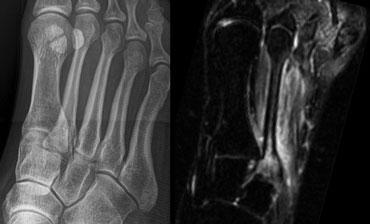

Bên trái là hình ảnh của bệnh nhân nữ 42 tuổi, thường xuyên đi bộ đường dài và bị đau vùng mu bàn chân trong một tháng.

Trên phim X-quang ban đầu không thấy đường gãy.

Sau 4 tuần, phim X-quang kiểm tra cho thấy rõ ràng sự hình thành can xương tại vị trí gãy xương do stress.

Bên trái là hình ảnh của bệnh nhân nữ 28 tuổi với khởi phát đau gần đây tại vùng xương đốt bàn chân thứ hai.

Tại thời điểm thăm khám, phim X-quang âm tính với gãy xương đốt bàn chân thứ hai.

Chuỗi xung MRI STIR (Short TI Inversion Recovery) cho thấy tăng tín hiệu tủy xương và phần mềm xung quanh, gợi ý phù tủy xương là hậu quả của gãy xương do stress.